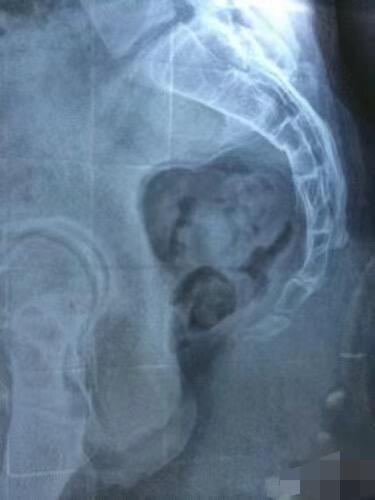

有很多人不能久坐 坐久了就会出现尾椎疼 其实尾椎疼有三个原因 第一像图二尾椎骨折有勾进去 坐着非常容易尾椎受力 第二像图三尾椎比较长的这种 坐着的时候如果不注意也容易压到尾椎 第三是骨盆后倾 骨盆后倾的时候支撑点在坐骨的后侧 这时候尾椎也容易被压到 当然第一二种情况往往会伴有骨盆后倾 前段时间有客户咨询我说坐着时候尾椎会疼 我就给她推荐无极骨盆矫正椅 她收到产品一试坐 感觉特别舒服再也不用压迫尾椎了 她是知道自己骨盆后倾导致的尾椎疼 并且又下单买了一把无极骨盆矫正椅